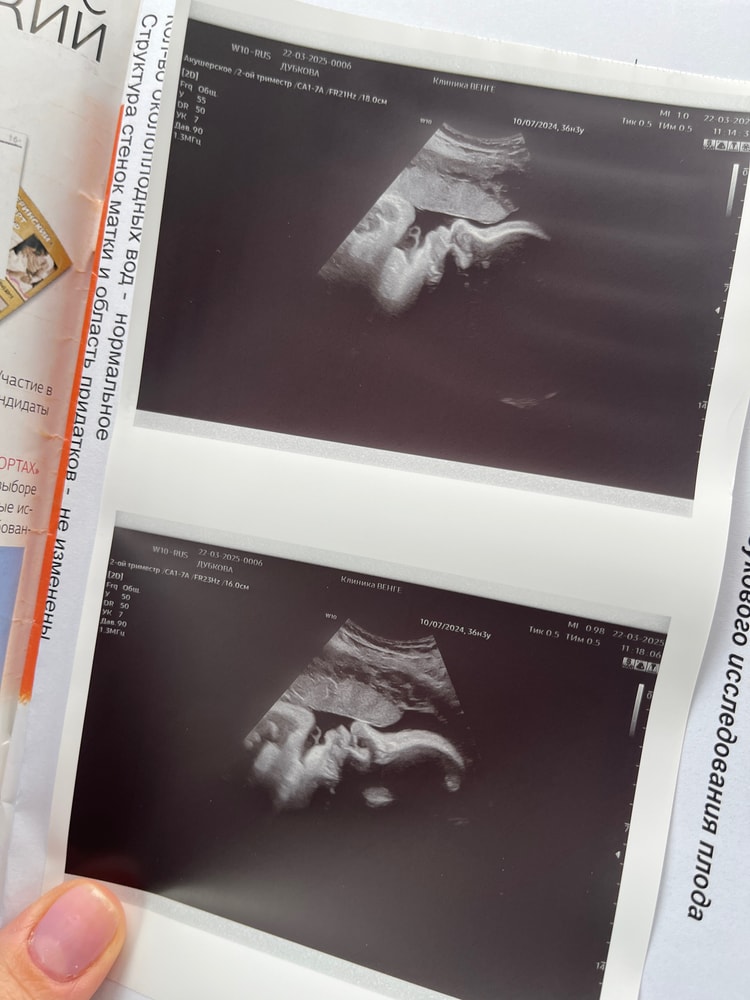

Узи 36.3

Вес малышки 3 кг 68 грамм, лежит вниз головой, однократное обвитие. А так, все хорошо. По скринингу срок опережает на неделю, поэтому и по узи ставят срок 37-38 недель. Врач сказала, еще смело можно ходить 2 недели.

Шейка 31, рубец состоятельный, 3 мм